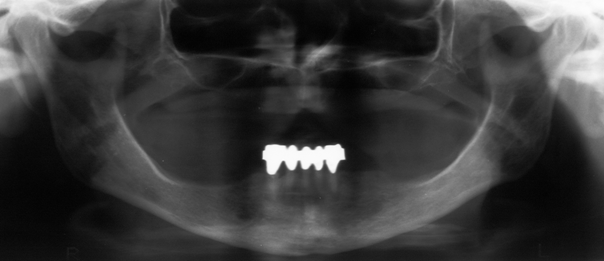

A 74-year-old edentulous woman with osteoporosis and fibromyalgia complained about growing pressure pain of the mandible following extraction of the lower anterior teeth and insertion of mucosa supported complete denture 6 months ago. Her medical history revealed 6 time administration of denosumab (Prolia® 60 mg) subcutaneously over the past 2.5 years. Fibromyalgia was treated with decortin. While intraorally no dehiscence was detected (Figure 1 [Fig. 1]), a panoramic view indicated irregular bone morphology especially in anterior mandible (Figure 2 [Fig. 2]) compared to preoperative imaging 10 months ago (Figure 3 [Fig. 3]). A CT scan illustrated the whole extent (Figure 4 [Fig. 4]). A RANK-Ligand inhibitor (denosumab) associated osteonecrosis of the mandible was diagnosed and reminded us of known BP effects on the jaw. Due to missing dehiscence she was treated conservatively with sultamicillin and prosthesis leave for 2 months with slight improvement of complaints. On the other hand with respect to the great extent of the osteonecrosis, we clarified the potential need of microvascular free flap for reconstruction.

Figure 3: Panoramic pre-extraction view with remaining anterior teeth 10 months ago